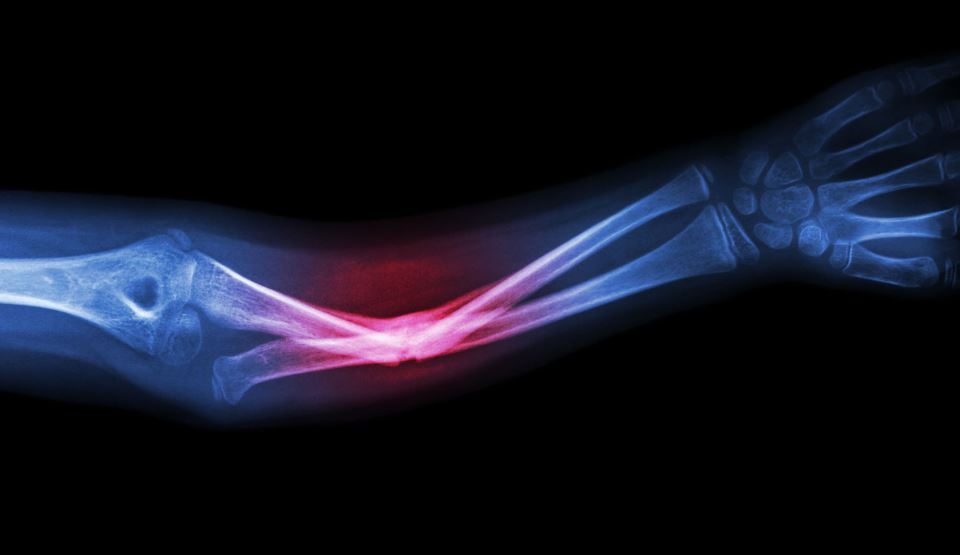

Una dintre cele mai frecvente fracturi ale omului nu este cea de picior cum ne-am gândi, ci fractura de pumn.

Dr.  Daniel Vîlcioiu Fractura de pumn reprezinta una din cele mai frecvente fracturi de la nivelul scheletului osos. Epifiza distala de radius are un rol esenţial în biomecanica pumnului şi de aceea este important ca fracturile la acest nivel, să fie tratate corect de la începutul tratamentului ortopedic. De reţinut este faptul că pacientul trebuie monitorizat obligatoriu pe parcursul tratamentului, pentru a exclude orice fel de complicaţie de tipul deplasării fracturii pe gips sau pierderea mobilităţii degetelor, putând alege conversia tratamentului ortopedic în tratament chirurgical. De asemenea, în cazul operaţiei de fixare a fracturii nu mai este nevoie de imobilizare postoperatorie, pacienţii putând mişca mâna liber, fără a face mari eforturi.